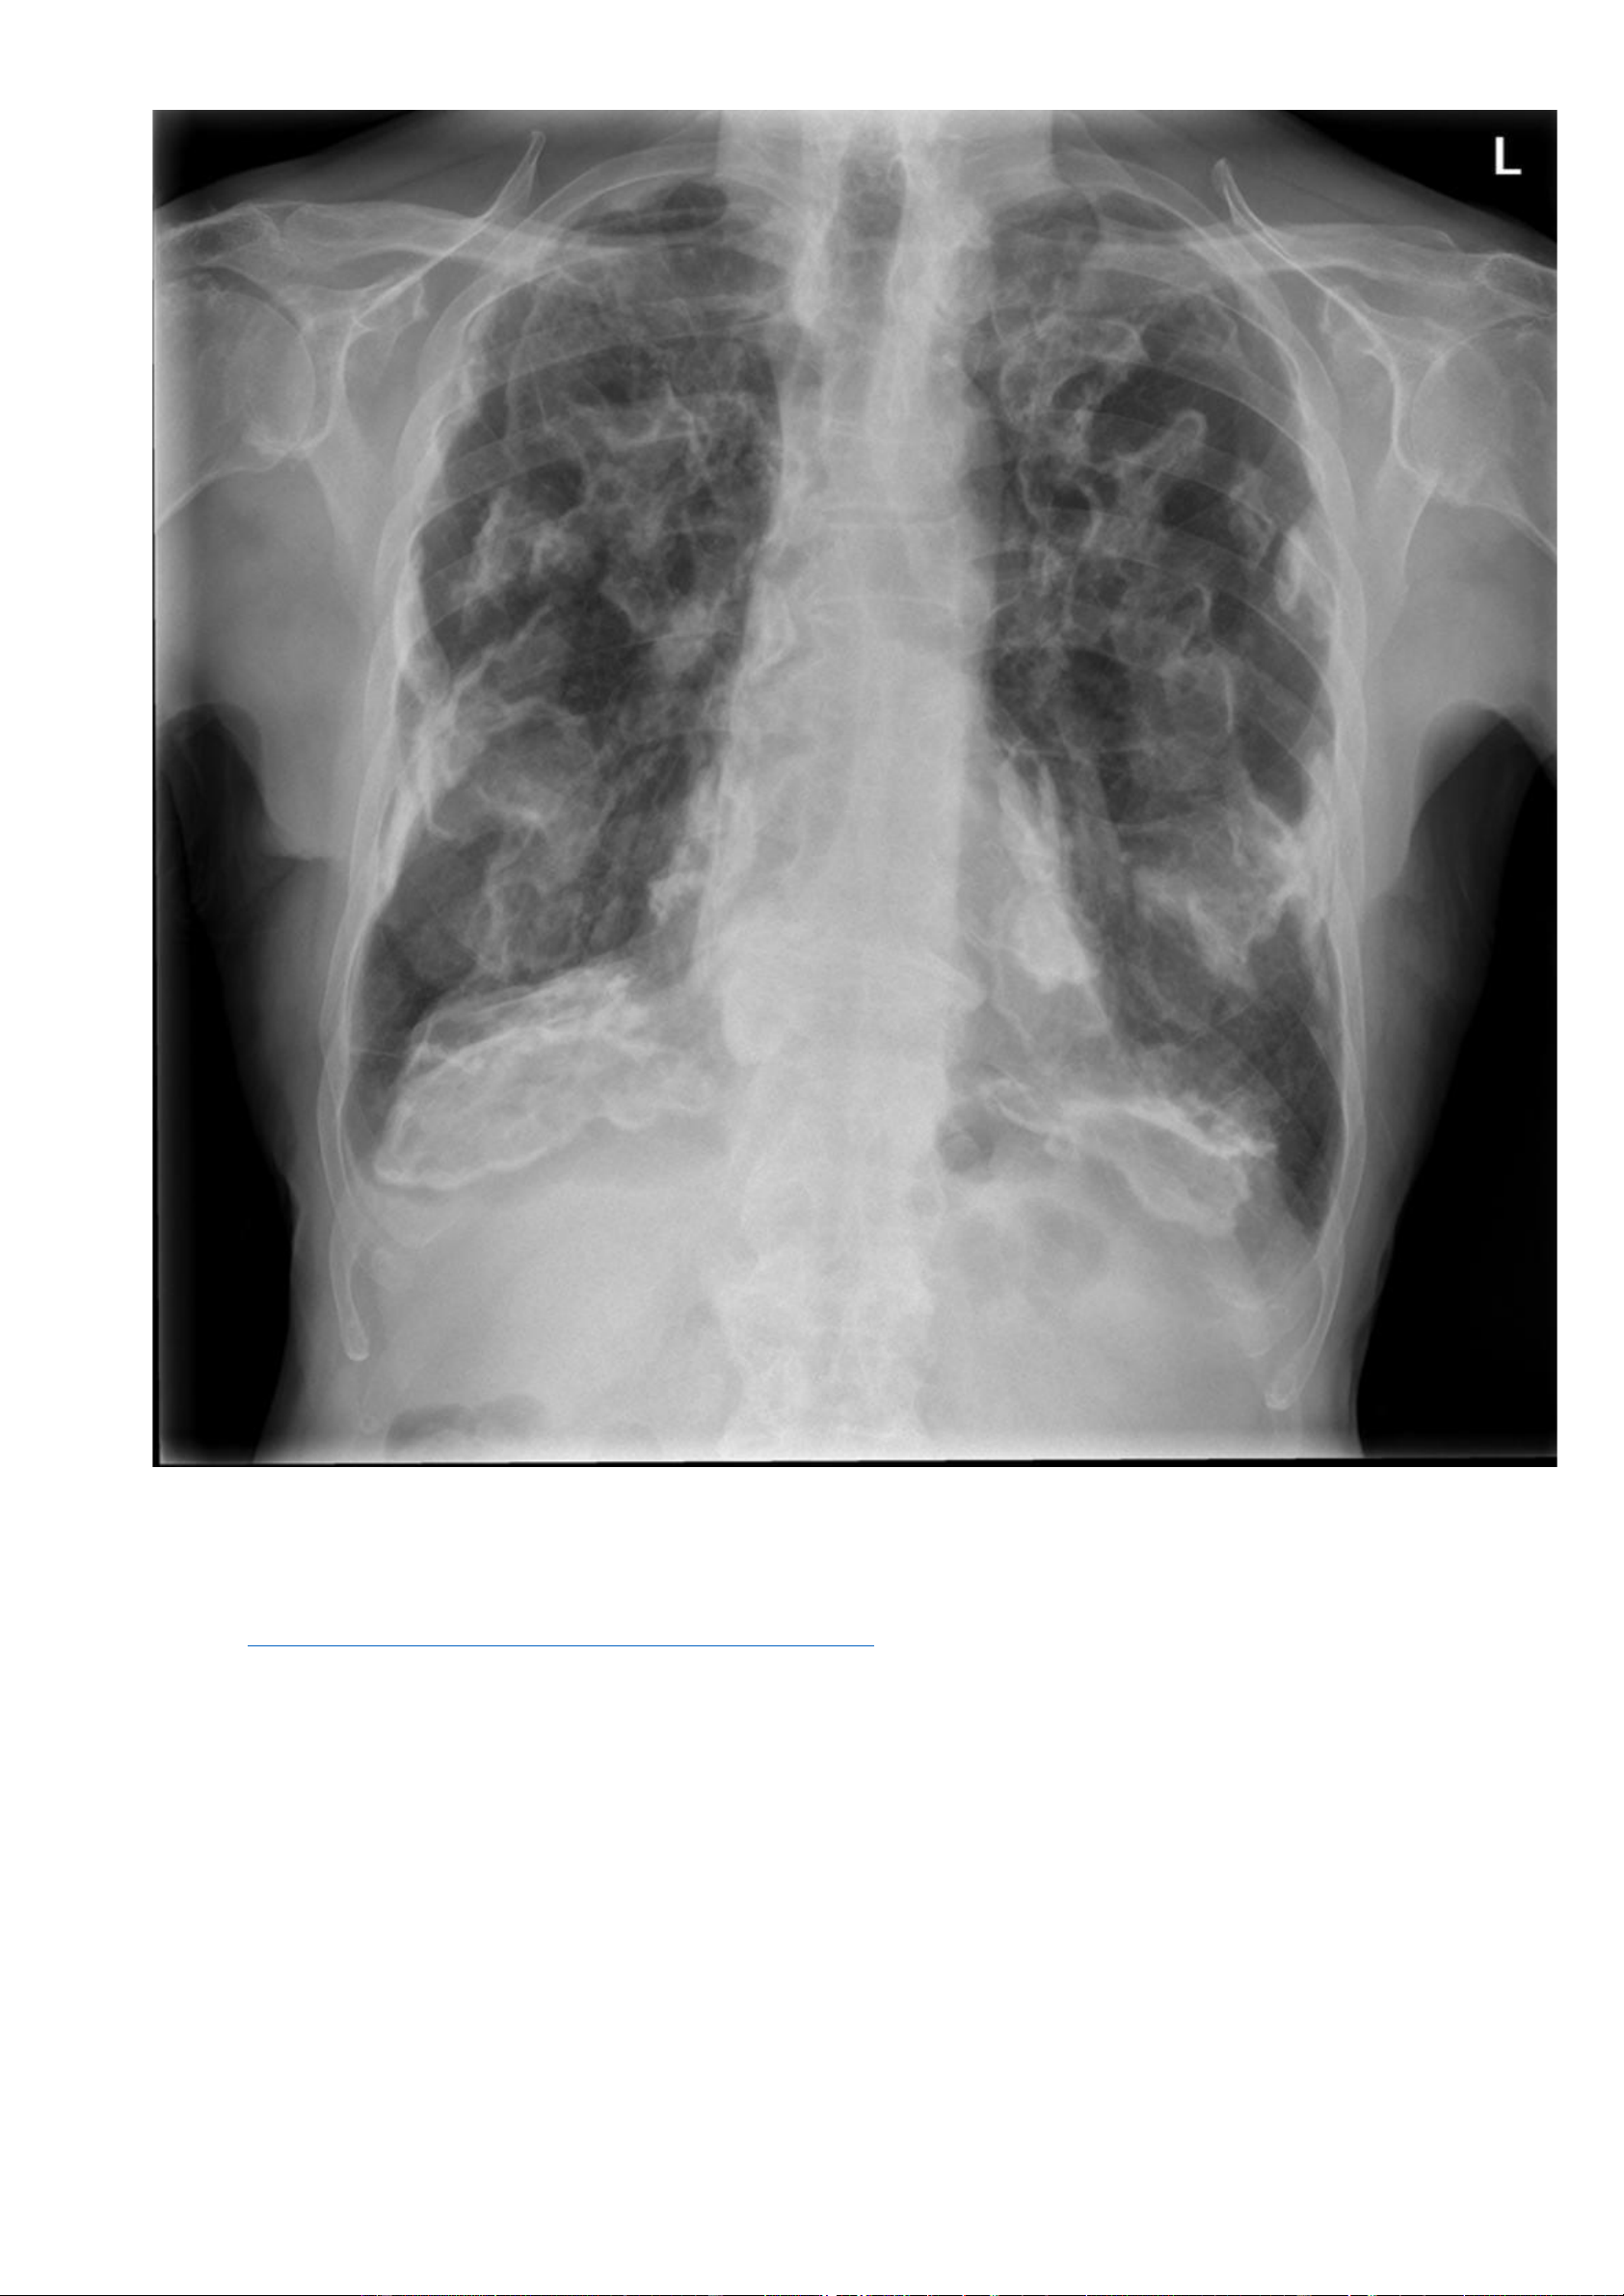

Nguồn link: https://radiopaedia.org/cases/calcified-pleural-plaques - Thông tin bệnh nhân: Không có. - Hình ảnh X quang:

Các hình mờ ranh giới không rõ ở vùng giữa và vùng dưới hai phổi. Vôi hoá dạng đường ở vị trí nửa cơ hoành 2 bên. -